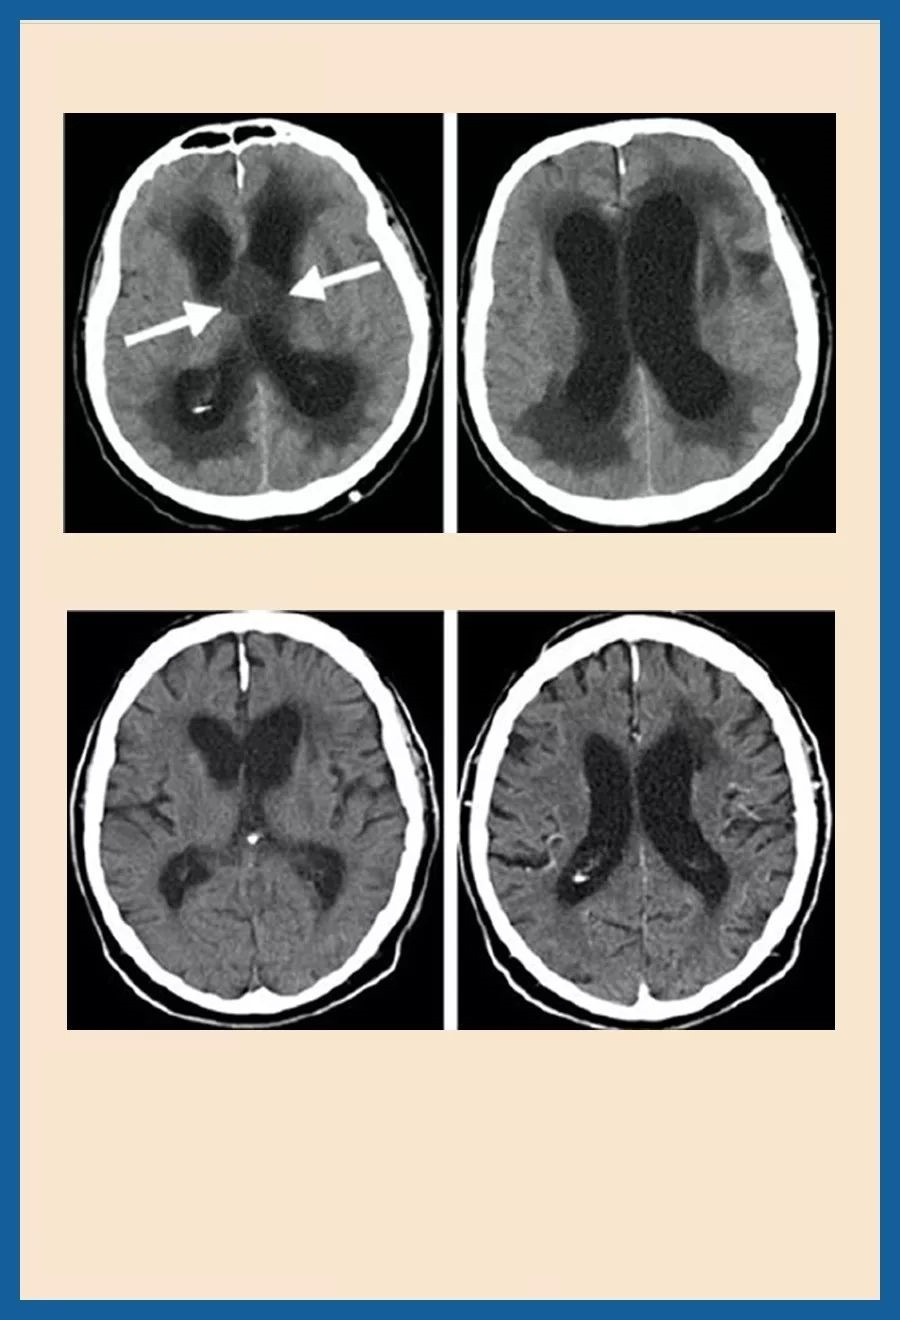

颅咽管瘤是一种具有良性组织病理学特征但呈现恶性临床行为的鞍区肿瘤。该肿瘤起源于垂体胚胎发育阶段残留的扁平上皮细胞,属于先天性颅内良性肿瘤...

现代神经外科手术之父哈维库欣(Harvey Cushing)把颅咽管瘤称为颅内最可怕的肿瘤。颅咽管瘤通常位于颅底深处,尽管病理学是良性的,但它却具有恶性肿...